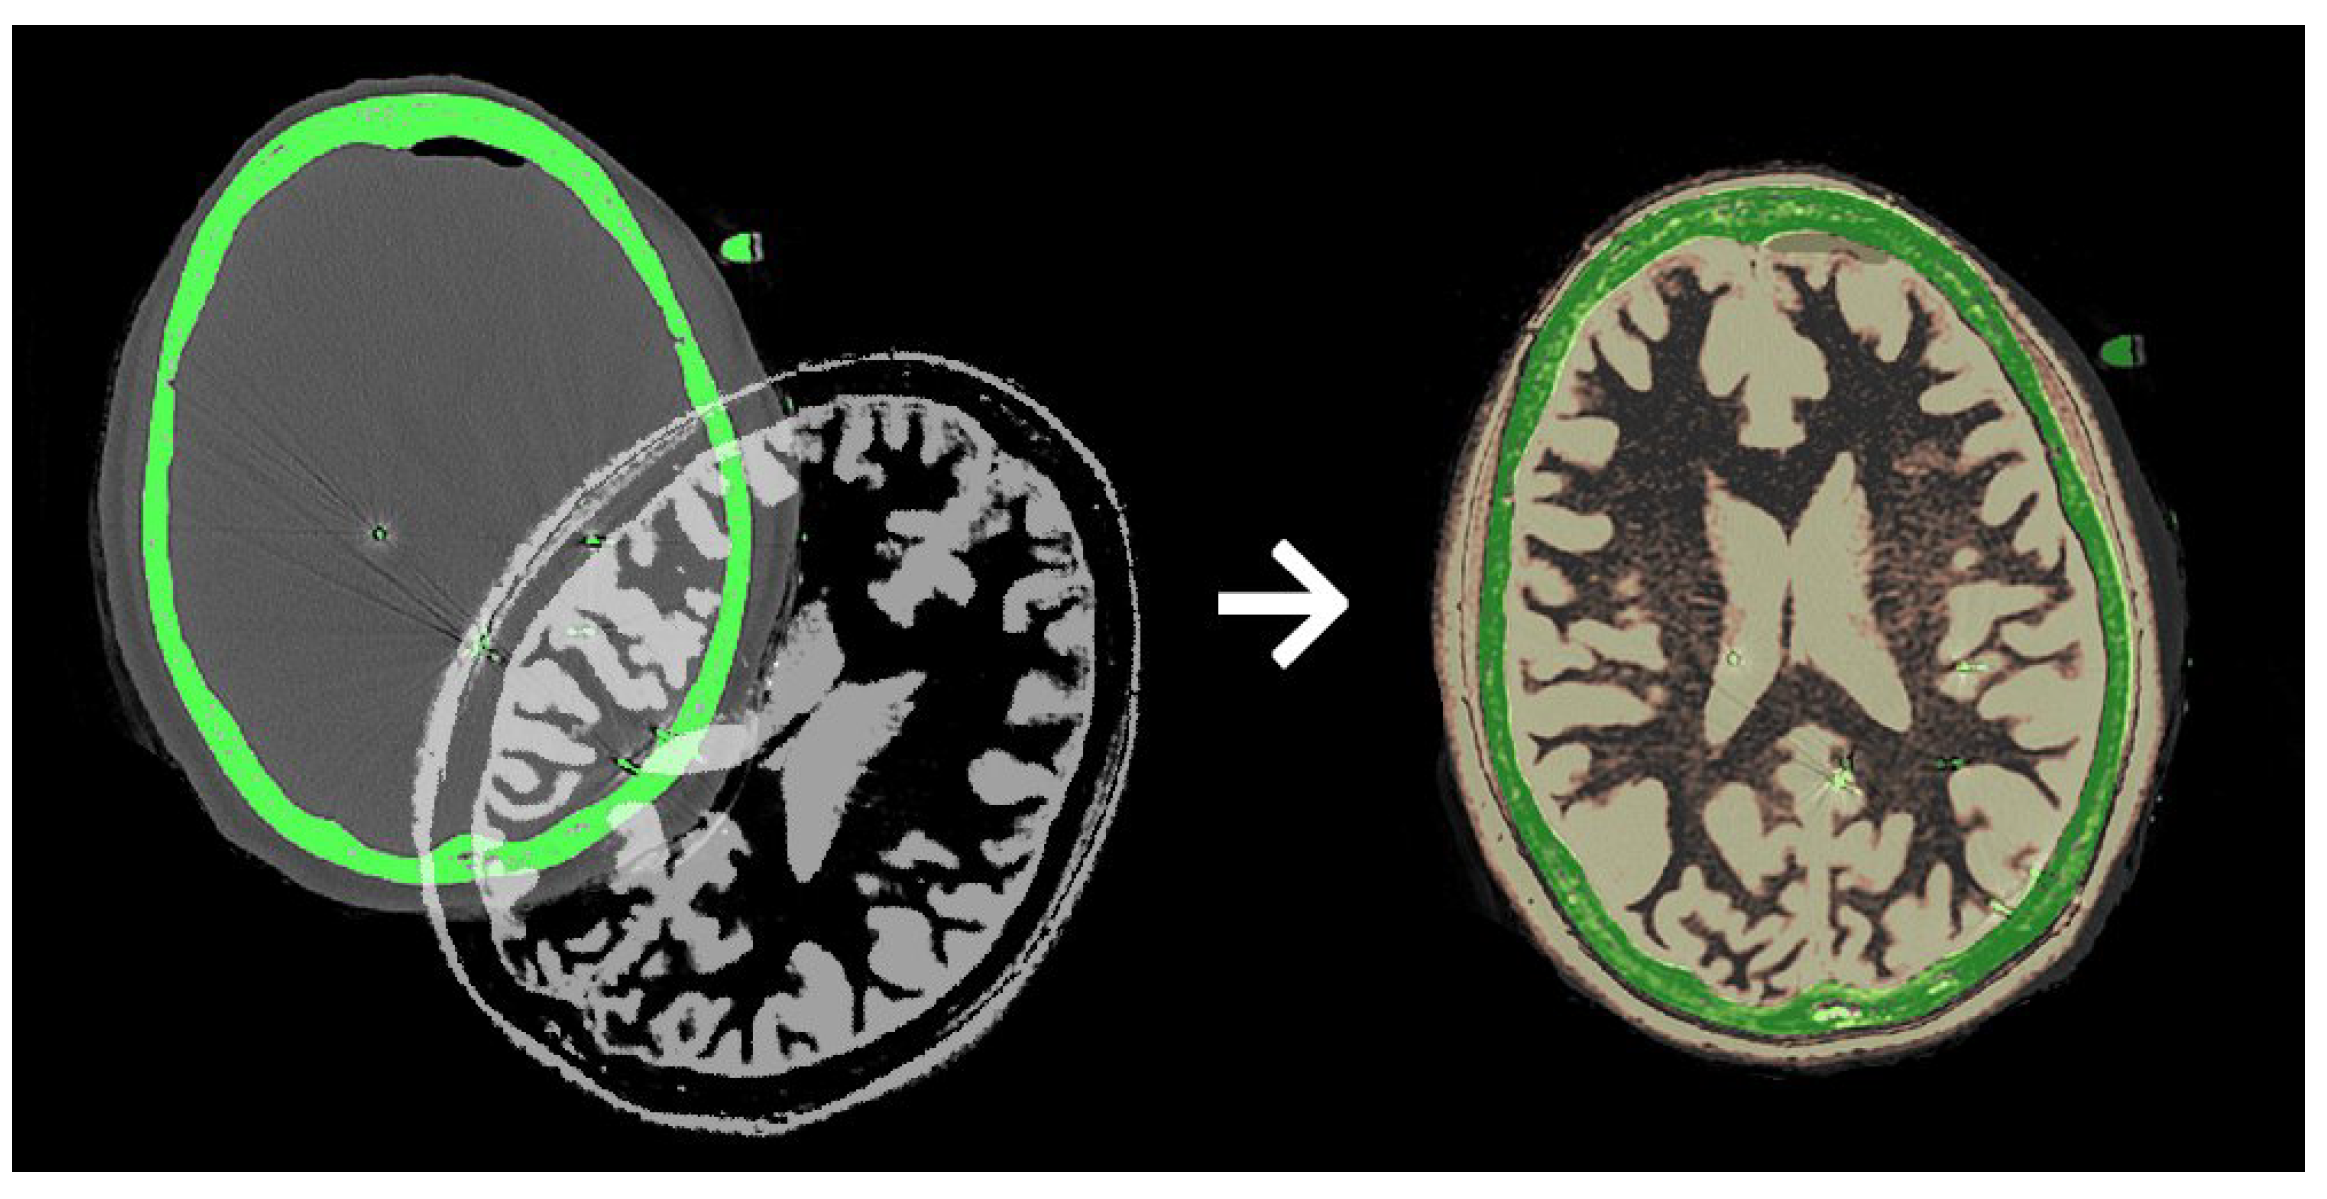

Global geometric transformations include shifting, rotation, scaling, or shearing. An example of global shifting and rotation is displayed in Figure 4 on CT and MR images.

Medical image registration is the process of aligning multiple medical images, volumes, and surfaces to a common coordinate system. In medical imaging, it is often necessary to compare multiple scans of the same patient acquired during different sessions and under varying conditions. At this point, medical image registration is typically used as a preprocessing step to align the medical images to a common coordinate system before analysis [24].

The brain MRI example above demonstrates a typical case of global geometric misalignment that can be corrected using standard rigid or affine transformations. However, medical imaging encompasses a wide range of modalities, many of which involve acquisition-specific distortions that cannot be resolved by global registration alone. To illustrate this broader challenge, we next present a mammography example, where compression-based shape deformation leads to local pixel displacements, making deformable (non-rigid) registration essential.

Figure 4. CT and MR imaging data (left) are unaligned before registration. Aligned data (right) show the correct anatomical positioning after registration [23].